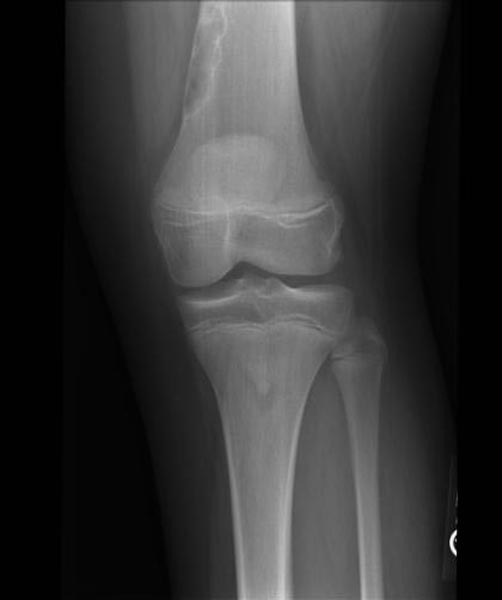

Welche Befunde erheben Sie auf dem vorliegenden Röntgenbild? Wie lautet ihre Diagnose? Müssen Sie eine weitere Abklärung initiieren?